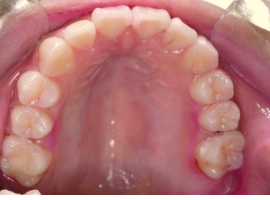

上顎

- After